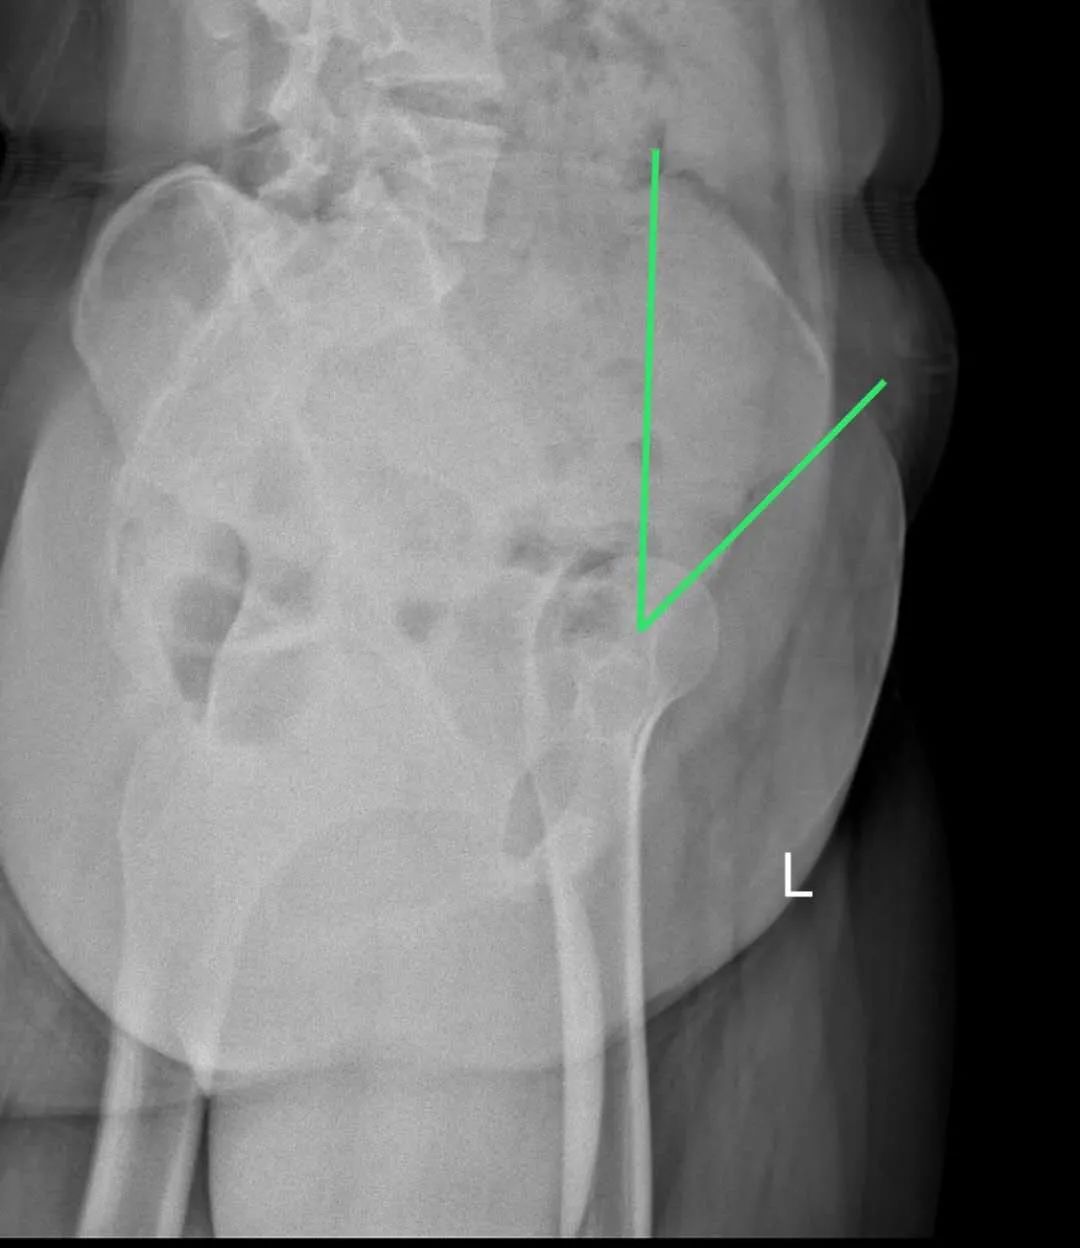

今年15歲的孫某,出現(xiàn)雙側(cè)髖部疼痛,呈持續(xù)性隱痛,只采取口服藥物的保守治療,但是疼痛未見減輕反而愈演愈烈,于是到誠德骨科醫(yī)院集團(tuán)(市中院區(qū))尋求專家的幫助,經(jīng)過多方檢查和論證后,劉德俊院長診斷為:

先天性多發(fā)性骨骺發(fā)育不良,并決定為其實施“髖臼周圍截骨術(shù)”。

術(shù)后